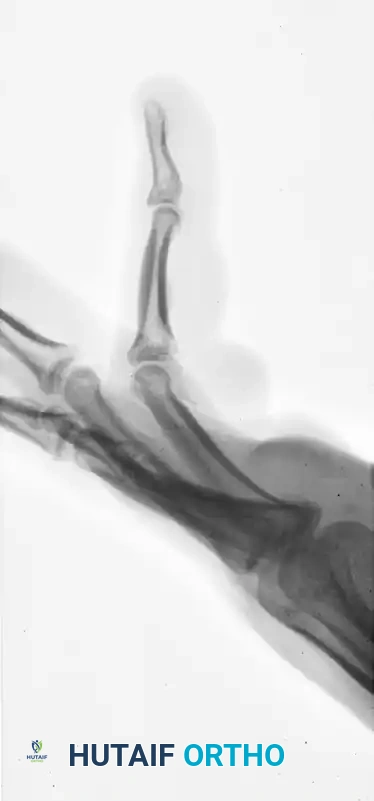

The following radiographs demonstrate a complex, three-part displaced intra-articular fracture of the proximal phalanx in a 27-year-old man. The articular surface is significantly disrupted, necessitating open reduction.

FIGURE 67-41 C: Preoperative lateral radiograph showing the volar subluxation tendency.